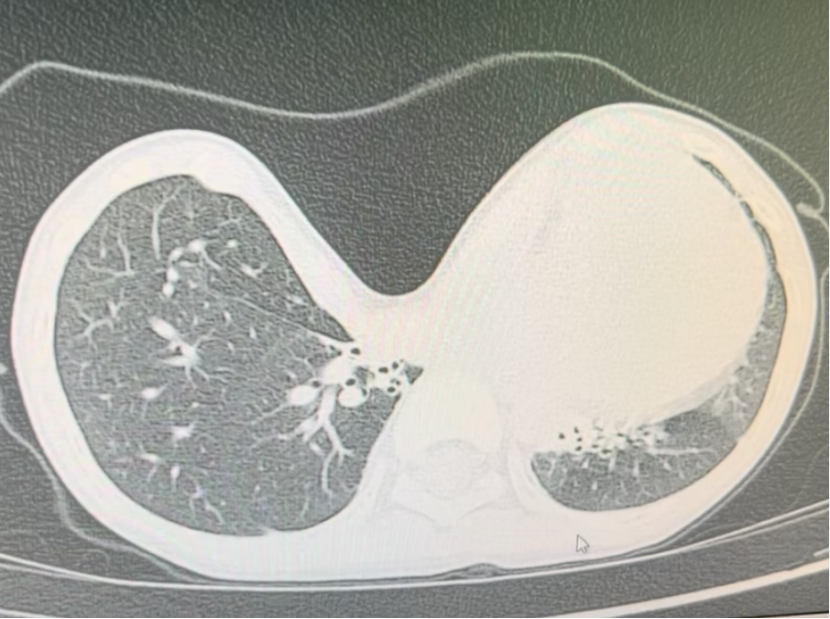

Pectus excavatum, commonly referred to as “funnel chest,” is marked by a prominent depression of the sternum and neighboring ribs. The exact cause of pectus excavatum is still unclear, but experts agree that early detection and treatment are crucial.

The pectus excavatum symptoms primarily involve both physiological and psychological aspects. In most cases, mild pectus excavatum does not cause serious health problems. However, in severe cases, it can manifest as chest tightness, shortness of breath, palpitations, and chest pain, among other respiratory and circulatory symptoms; severe or long-term deformity may also lead to scoliosis. Psychologically, it commonly leads to low self-esteem, anxiety, and social avoidance and can potentially develop into long-term psychological problems.